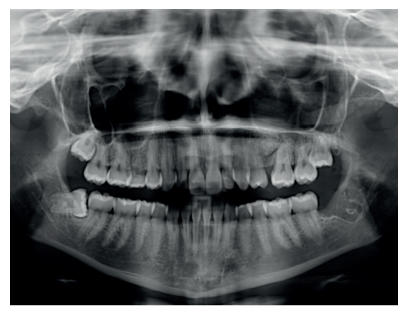

Caso clínico: se presenta un caso clínico de una mujer de 20 años, sin antecedentes médico-quirúrgicos de interés, que acudió a consulta remitida por su ortodoncista, para la extracción de un premolar maxilar retenido, en posición invertida. Tras la extracción del premolar y del tercer molar inferior retenidos, se obtuvo dentina procedente de ambos, para la regeneración ósea guiada del defecto resultante de la extracción del premolar, realizando revisiones a la semana y a los 4 meses de la intervención.

Clinical case: a clinical case of a 20-year-old woman is presented, with no interesting medical record, who went to dental clinic for removal of an inverse maxillary bicuspid retained. After maxillary bicuspid and lower third molar extractions, autogenous dentin was obtained from both teeth, to perform a guided bone regeneration of the bicuspid defect. A week and 4-month check-up were carried out.

El objetivo de este caso clínico es presentar la eficacia de la dentina autógena como material de injerto en un procedimiento de ROG, tras la exodoncia de un premolar superior izquierdo retenido, en posición invertida.